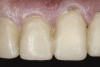

(38.) Postoperative right anterior, close-up view.

Figure 38

(39.) Postoperative anterior, close-up view.

Figure 39

(40.) Postoperative left anterior, close-up view.

Figure 40